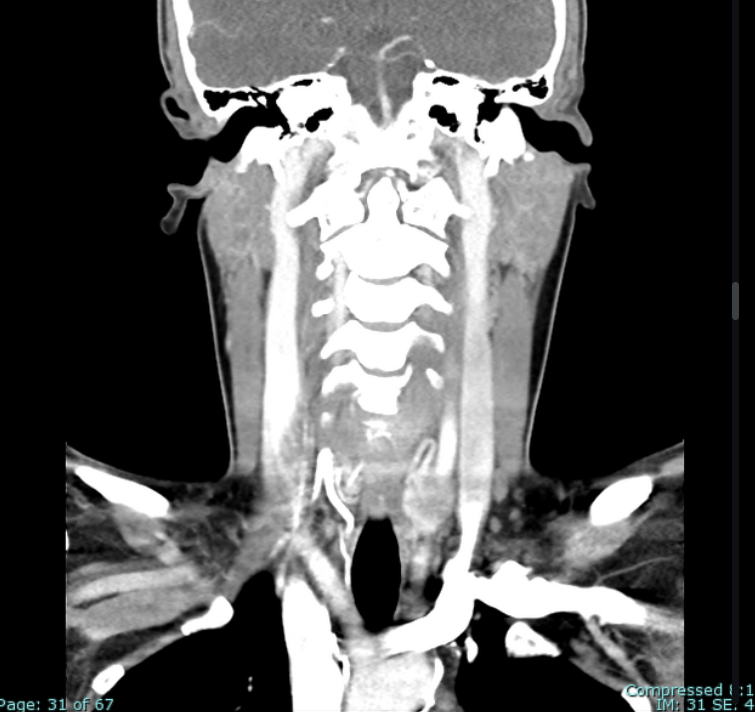

Coronal C+ portal venous phase

• Title: Neck pain and swelling

• Diagnosis Title: Medullary thyroid cancer